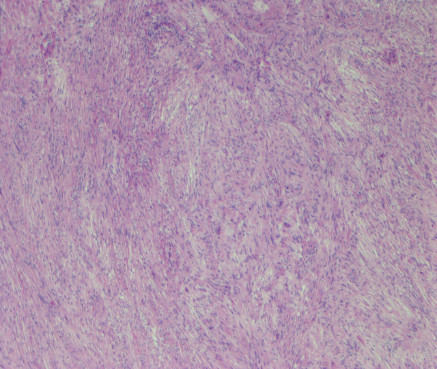

Cortesía de la Dra. Claudia Haydée Caro Sánchez, del INCAN.

Mujer de 57 años, con dolor abdominal leve de predominio postprandial. En la tomografía computada se evidenció una lesión en curvatura menor de 5 cm, dependiente de la pared. No se realizó biopsia y se programó para resección de lesión en cuña.

1.- ¿Cual es el abordaje diagnóstico por tinciones de rutina?

a) leiomioma

b) schwannoma

c) tumor glómico

d) tumor del estroma gastrointestinal.